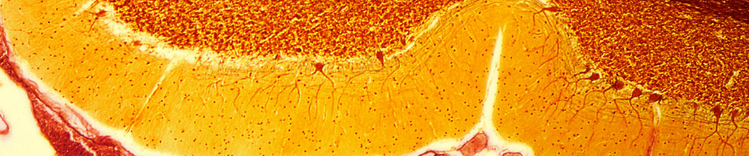

CÉLULAS DE PURKINJE NO CEREBELO

As mudanças físicas no cérebro associadas ao envelhecimento incluem:

- Atrofia (diminuição) do tecido cerebral de algumas regiões

- Aumento do volume ventricular

- Perda de neurônios e sinapses e redução na formação de novos neurônios

- Acúmulo de proteínas anormais